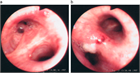

1. 肺がんの危険因子が多い患者では無症状でも胸部CTなど詳細な陰影の質的な評価と単純X線写真でとらえられないその他の異常所見の確認もする(推奨度1)

1. 肺がんの危険因子の乏しい患者での3cm以下の石灰化を伴う結節影は良性のことが多い(推奨度1)

1. 迅速に出現した結節影は円形肺炎を考える(推奨度1)